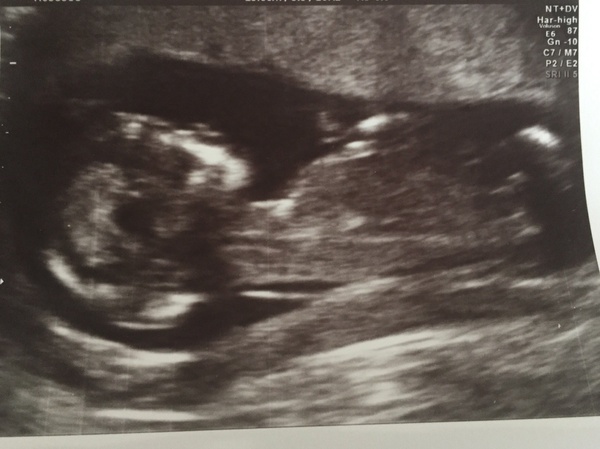

Finally had scan! Edd now 19th December Smile

December 2016 babies... 2nd trimester in sight

Finally, Ive had my scan EDD 21st December so I'm 12+5 baby was cute, stretching and waving arms but the ultrasound was much more blurry than I expected. I feel a bit disappointed with the photo, maybe the 20 week one will be more clear.